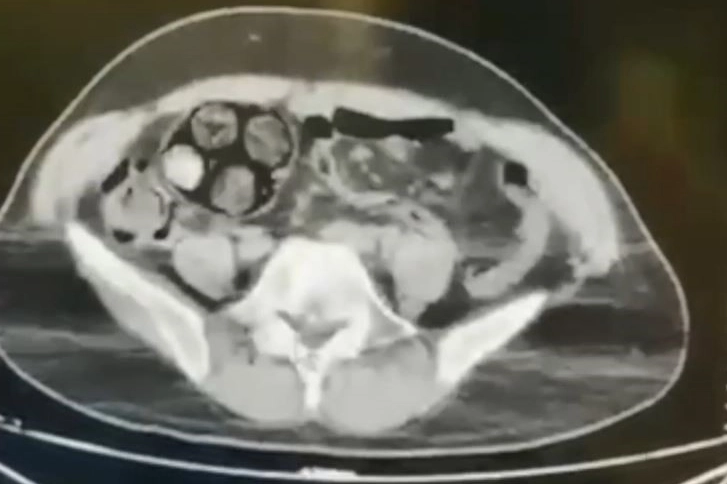

Artvin’de düzenlenen operasyonda yakalanan İran uyruklu şahsın yuttuğu 10 paket uyuşturucu cerrahi müdahale ile çıkarılarak, şüpheli gözaltına alındı. Edinilen bilgiye göre, Artvin İl Jandarma KOM Şube Müdürlüğü ekipleri, İran uyruklu Farshid Rafıeıeınsheykh (43) adlı şüphelinin 8 Mart tarihinde vücudu içerisine uyuşturucu madde gizleyerek Artvin’e getireceği bilgisi üzerine çalışma başlattı. Yapılan takip sonucu Artvin merkez Çayağzı Mahallesi’nde yakalanan şüphelinin üst aramasında herhangi bir suç unsuruna rastlanmadı. Bunun üzerine şüpheli, Ceza Muhakemesi Kanunu'nun 75. maddesi gereği iç ve dış beden muayenesi için Artvin Devlet Hastanesine sevk edildi. Çekilen tomografi sonucu zanlının bağırsaklarında 10 paket tespit edildi. Cerrahi müdahale ile çıkarılan paketlerin içinde toplamda 350 gram metamfetamin maddesi olduğu belirlendi. Gözaltına alınan İranlı zanlı hastanede müşahede altına alınırken, olayla ilgili soruşturma başlatıldı. Zanlının hastaneden taburcu olmasının ardından hakim karşısına çıkarılacağı bildirildi.